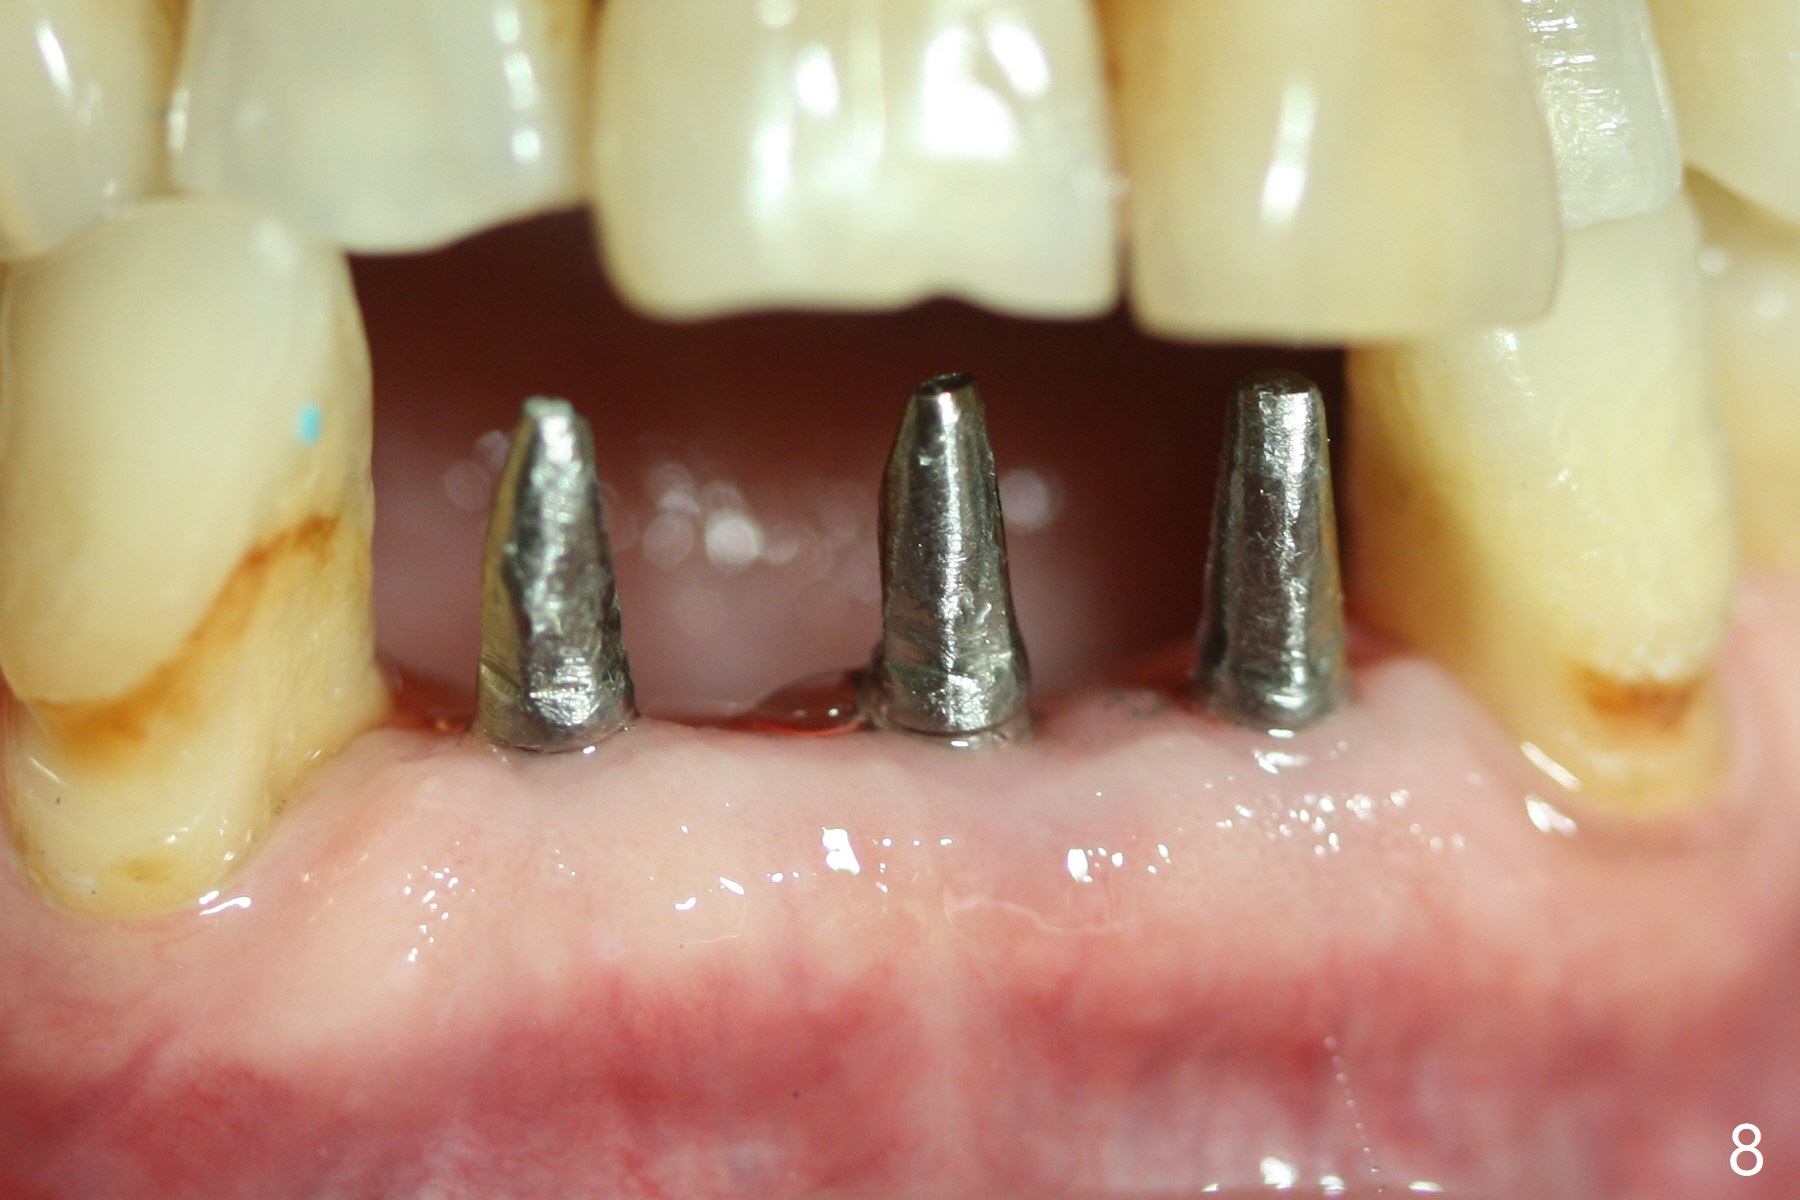

When the patient returns, the tooth #24 has exfoliated, while the ones at #25 and 26 has mobility III (Fig.1). The patient requests the tooth #23 extraction (Fig.2), but not #27. After SRP and extraction, osteotomy is initiated mesial to the sockets #23,25 and 26 (Fig.3,4) with intention to place 3 1-piece implants for 3 incisor crowns (Fig.5,6). Following Vanilla graft (Fig.5 *) a splinted provisional is fabricated to close the sockets (Fig.6). Peri-implant spaces close 5.5 months postop (Fig.7). Impression is taken after reprep for margin and parallelism (Fig.8). The final restoration consists of #23 single unit crown and #24-26 3-unit FPD (Fig.9). It appears that 2.5 mm 1-piece implants are not too small for the lower incisors (Fig.10-12), especially the central one (Fig.11). There may be perforation in the apical half of the lingual plate (L in Fig.10). The patient is not pleased with the shade of the #24-26 3-unit FPD (Fig.13 (6 months post cementation)). There is metal show through the abutments (*).